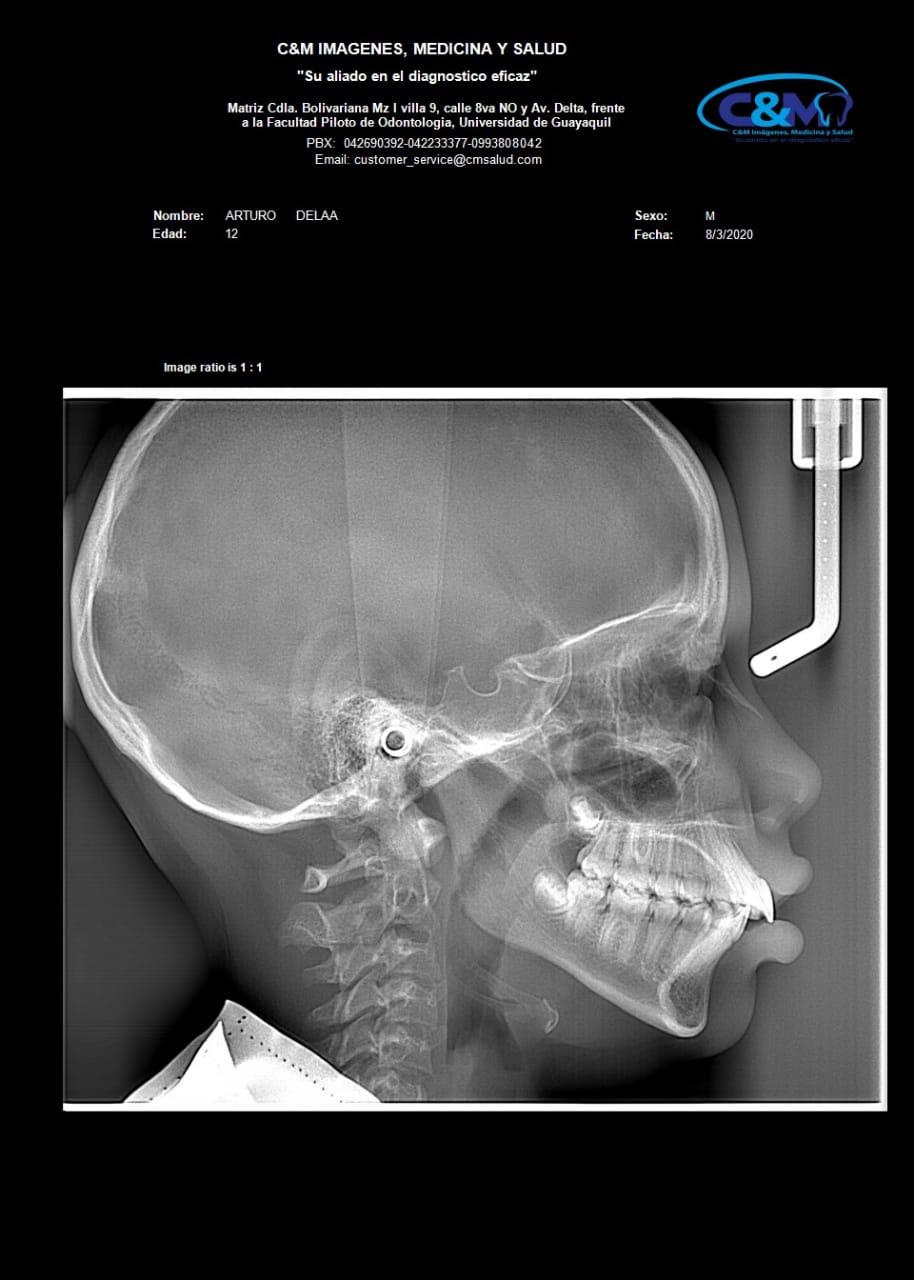

LATERAL DE CRANEO